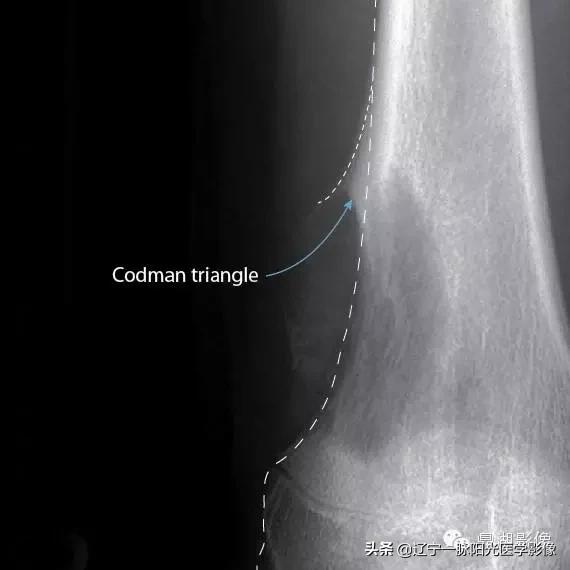

2.5.Codman三角:为肿瘤上下两端套袖样反应骨,X线上为骨干两侧三角形骨膜反应,表示病变已侵犯骨膜下皮质外。多数情况下为恶性肿瘤突破皮质,侵入软组织,偶可见于急性骨髓炎和骨膜下血肿。

见过最典型的Codman三角